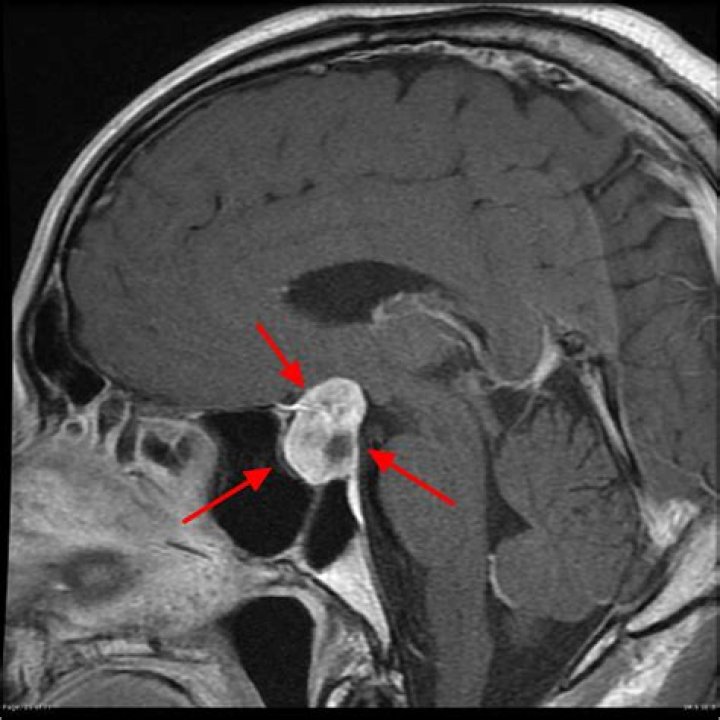

Where are pituitary tumors located?

Pituitary adenomasPituitary adenomas Pituitary tumors have very few known risk factors, and these are related to genetics. There are no known environmental or lifestyle-related risk factors for pituitary tumors. Though science has suggested that people who are overweight or obese might be at increased risk. › causes-risks-prevention › risk-factors

. These benign tumors do not spread outside the skull. They usually stay in the sella turcica (the tiny space in the skull that the pituitary gland sits in). Sometimes they grow into the boney walls of the sella turcica and nearby tissues, like blood vessels, nerves, and sinuses.

When pituitary tumors grow they can compress the above-mentioned structures and cause symptoms. Figure 1. A cross-section of the pituitary gland (green) shows its relationship to the optic chiasm, the sphenoid sinus, and the cavernous sinuses on each side.